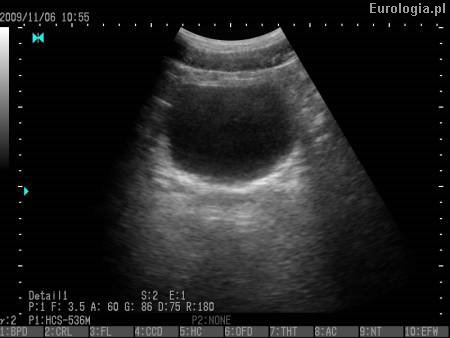

Fot. Gładkościenny pęcherz moczowy - obraz ultrasonograficzny.

W przytoczonym opisie USG lekarz nie stwierdził patologii pęcherza moczowego. Pęcherz w badaniu USG powinien być o gładkich ścianach. Dodatkowo nie stwierdzono zalegania moczu po mikcji co oznacza, że pęcherz opróznia się. Interpretacja wyniku badania USG powinna być ustalona w oparciu o wywiad i badanie przedmiotowe. Dalsze leczenie powinno być prowadzone pod kontrolą lekarza rodzinnego lub urologa.